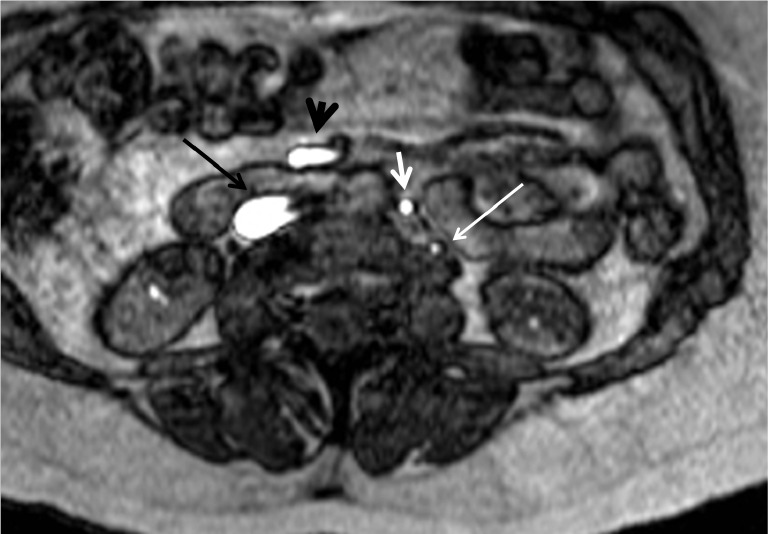

Figure 7.

Axial TOF image at the level of mid-abdomen. On this acquisition cephalad flow results in flow related enhancement. Inferior vena cava (long black arrow), Superior mesenteric vein (short black arrow) and inferior mesenteric vein (short white arrow) show bright signal because of cephalad flow. Similarly normal cephalad flow in left gonadal vein (long white arrow) results in bright signal. TOF, time of flight sequence.